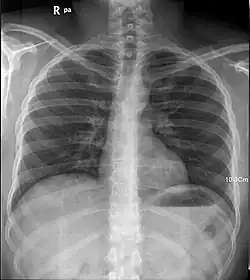

La radiografia classica è una specie di fotografia in cui il fascio di raggi X, emesso da una sorgente, attraversa l’oggetto sotto esame per poi colpire una lastra fotografica. L’oggetto, ossia il paziente, non è omogeneo ma composto da tipi di tessuti diversi e perciò attenua il fascio in modo variabile a seconda del tessuto colpito. Il tessuto osseo, ad esempio, assorbe una buona parte dei raggi X che lo attraversano, mentre i tessuti molli sono più trasparenti. I fotoni che non vengono assorbiti riescono ad arrivare sulla lastra e la impressionano.

Nella fotografia classica, dove la pellicola viene impressionata, essa si annerisce ottenendo quindi l’immagine negativa. Anche nella radiografia a raggi X si ottiene un’immagine nella quale le regioni maggiormente colpite da fotoni risultano scure, mentre quelle in cui il fascio è stato attenuato (per esempio da un osso) rimangono chiare.